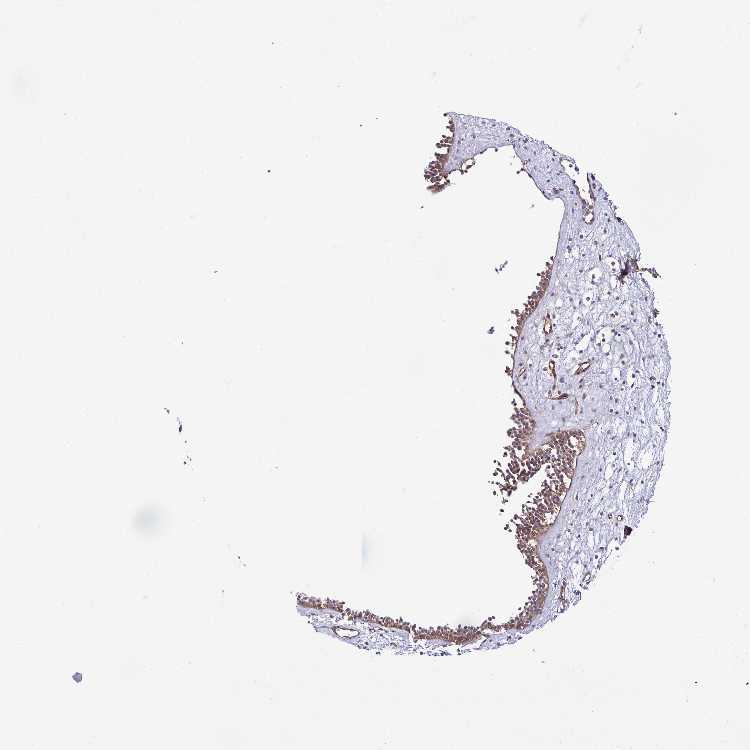

NASOPHARYNX - Antibody stainingi

Antibody staining in the annotated cell types in the current human tissue is reported as not detected, low, medium, or high, based on conventional immunohistochemistry profiling in selected tissues. This score is based on the combination of the staining intensity and fraction of stained cells.

Each image is clickable and will lead to virtual microscopy that enables deeper exploration of all samples and also displays staining intensity scores, fraction scores and subcellular localization as well as patient and tissue information for each sample.

Antibody HPA056819

Respiratory epithelial cells Medium